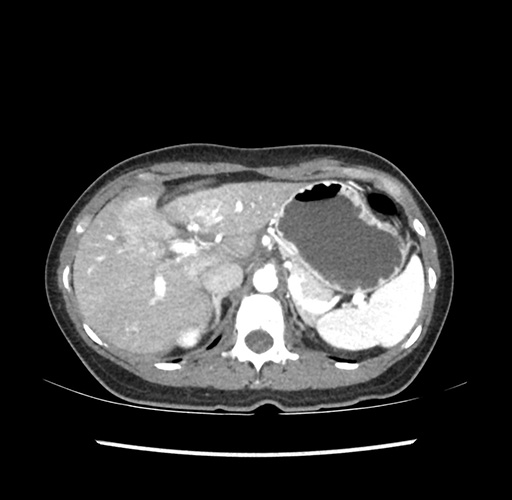

Left lateral sectionectomy [case 12]

Imaging Analysis

Look through the patient's CT scan to identify any areas of concern for the necessary procedure.

Based on your CT findings, which issue(s) would give reason for "planned slowing down moment(s)" in this case?

Considering a standard left lateral sectionectomy procedure, what step(s) of the operation would you do differently in this case ?